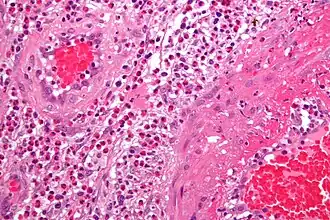

| Micrografia da vasculitite Síndrome de Churg-Strauss | |

- Síndrome de Churg-Strauss;